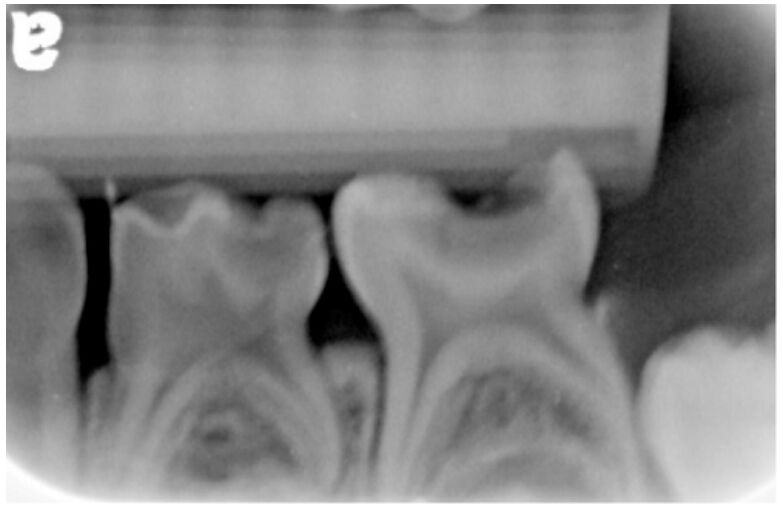

34.5歲女童上週吃巧克力後抱怨左下方牙痛,去刷牙後改善,這幾天不痛了;今日就診拍攝之放射線影像如 圖。關於該患處的敘述,下列何者最正確?

(A)第一乳臼齒在牙髓處理後應施作不銹鋼牙冠(SSC)或二氧化鋯牙冠(zirconia crown) (B)第二乳臼齒診斷為不可逆牙髓炎(irreversible pulpitis) (C)就診日當天應有膿腫(abscess)形成 (D)這幾天不再牙痛的原因是牙髓壞死